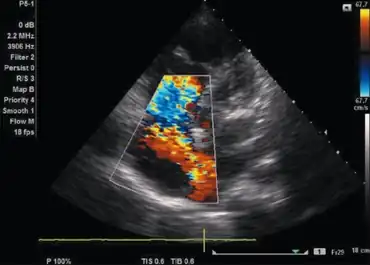

Lutembacher's syndrome showing flow from left atrium to right atrium through atrial septal defect

Lutembacher's syndrome is diagnosis primarily by physical examinations for heart sounds, electrocardiograms, chest radiogram, transthoracic or transesophageal echocardiography, color flow mapping, and Doppler imaging. Use of the various test can help to differentiate other possible conditions such as mitral regurgitation, Ebstein disease, ventricular septal defect (VSD).[9]

Color flow mapping and Doppler imaging

A color flow and doppler imaging is used to help confirm the presence as well as evaluate the severity of ASD and MS.[9]